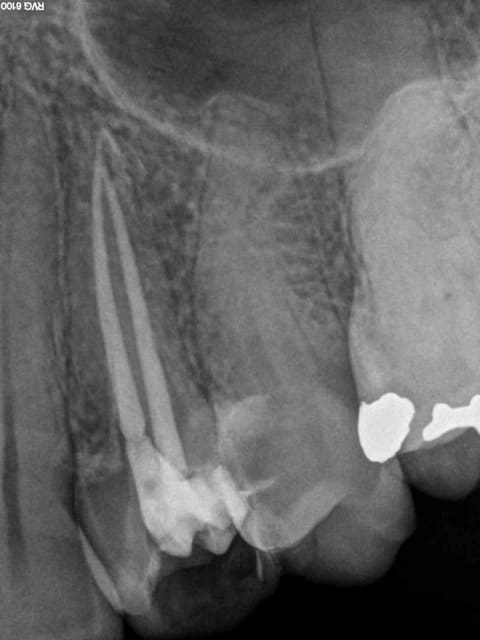

C'est un traitement conforme aux recommandations de la HAS. Celui ci n'est pas conforme : pourquoi ?

Et pourtant obturation à l'apex, thermo-compaction.

Il est au tarif secu ?? Sans digue .

Si on parle d'expertise medicale seule, il y a perte de chance par la non mise en place de la digue qui à elle seule entraine la responsabilité du praticien.

+ pas de reconstitution préendo.-)))